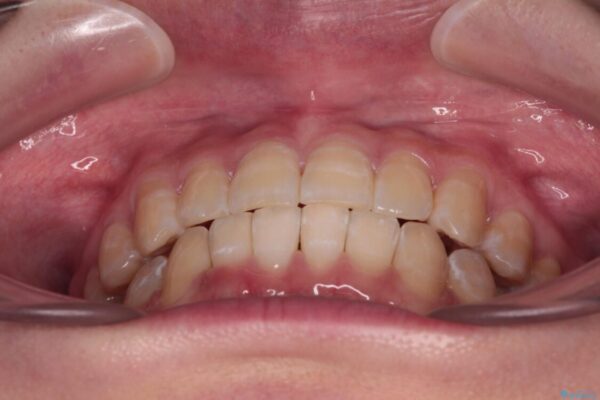

下顎の八重歯を気にして来院された患者様です。

下顎前歯にデコボコが集中していたため、顎間ゴムによる後方移動とIPR(歯と歯の間を削ること)により歯列を整えることとしました。

治療前、下顎前歯のデコボコが集中しており、奥歯の咬み合わせは、上顎に対して下顎が前方位にある状態でした。下顎の歯列を後方へ移動させる治療はインビザラインの得意とするところですので、1年程度で無事に治療を終えることができました。

• 【モニター】下顎前歯のデコボコをインビザラインできれいに 治療前画像